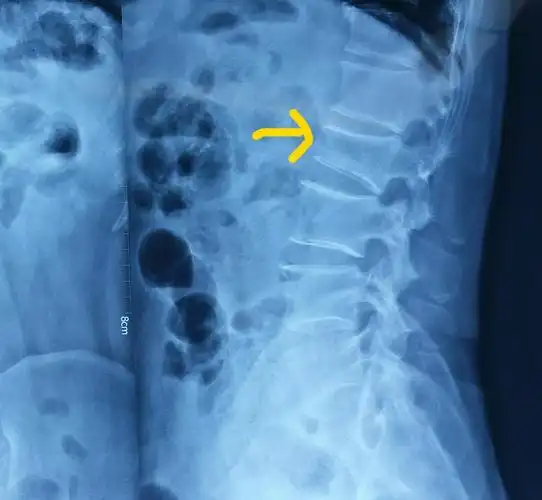

腰椎压缩性骨折新鲜

38床, 腰1椎体压缩性骨折

术前x线平片示腰2椎体明显压缩骨折,压缩约1/2.

腰椎压缩性骨折新鲜原创